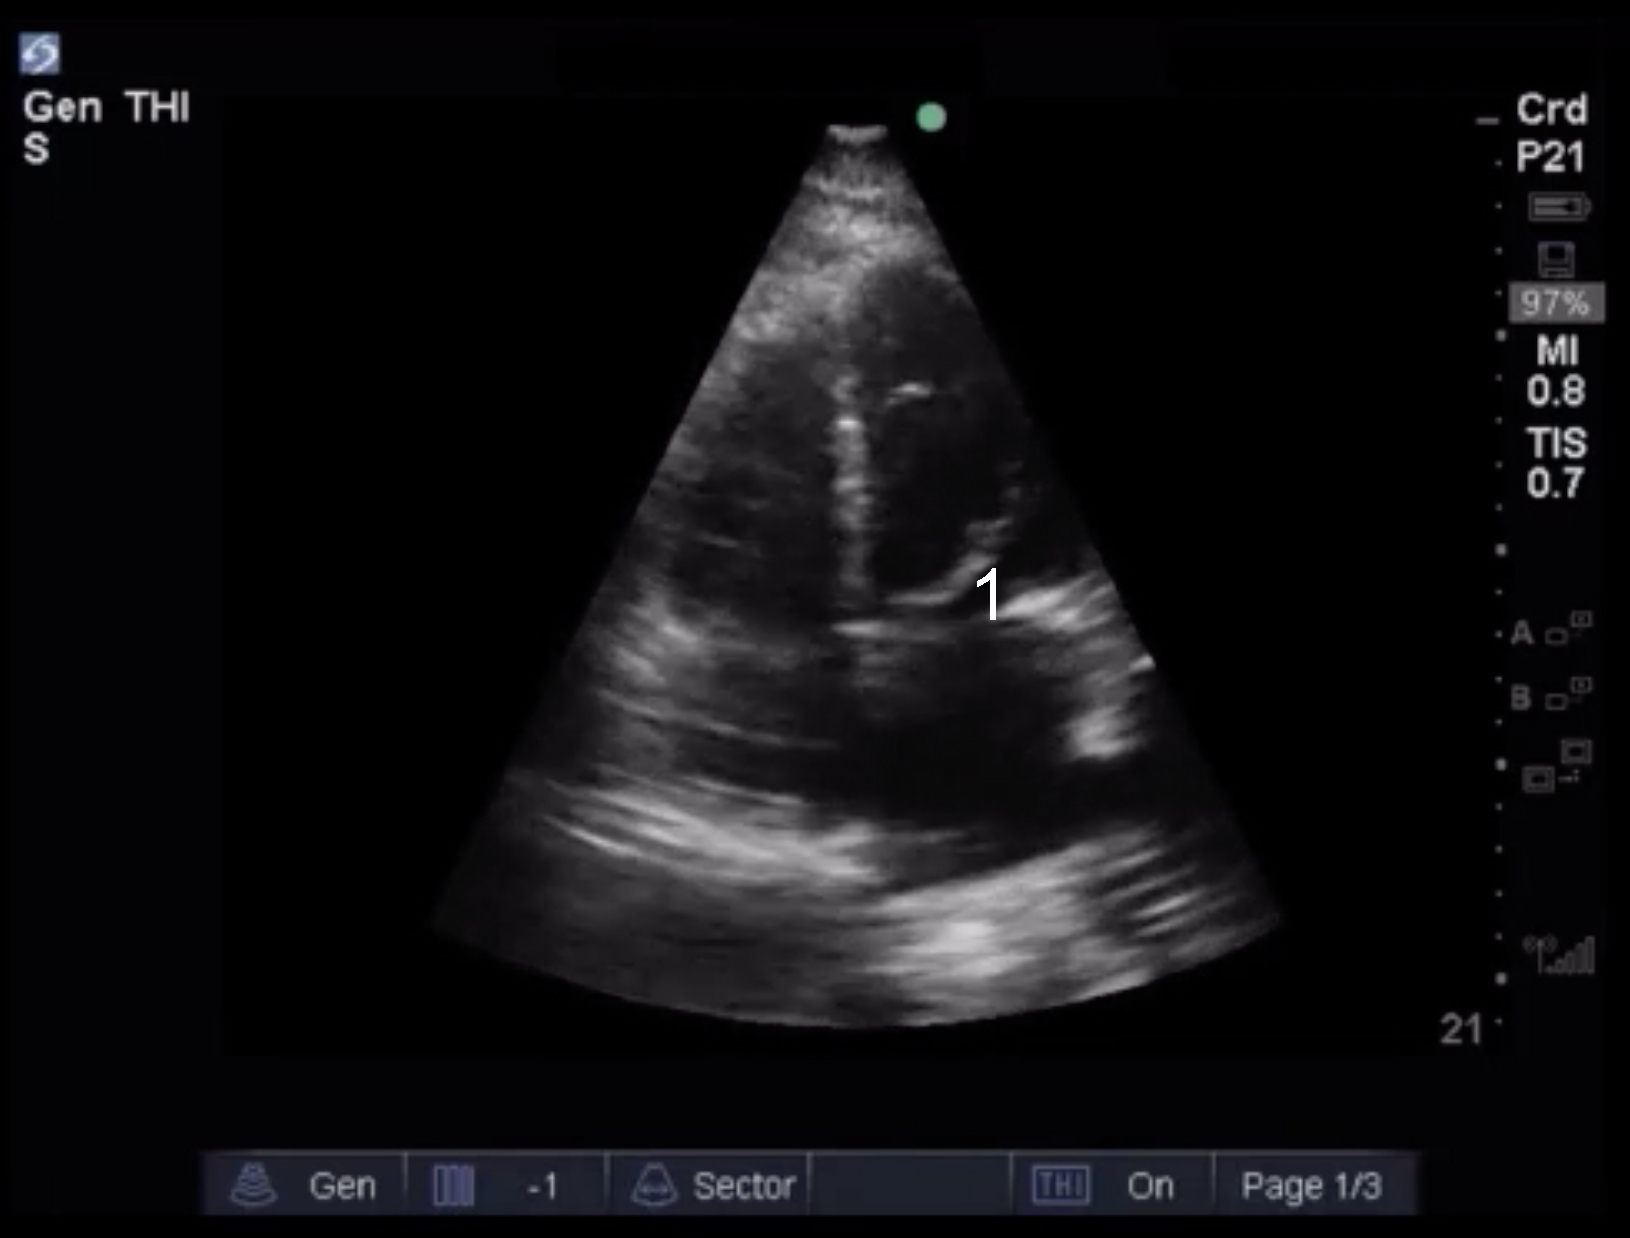

Cardiac 2 Valves Eyeball Assessment Example 5 Image

Mitral Valve